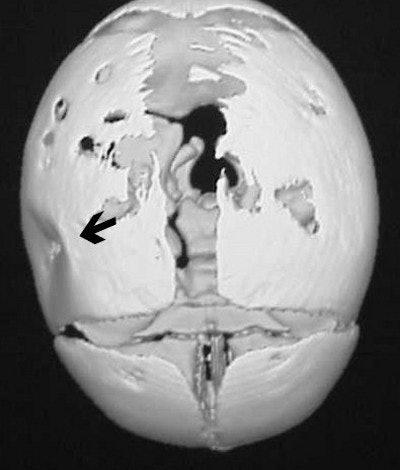

How about CT imaging for an in vitro trauma? Figure CT 5 is an axial image of a newborn child; there were no problems during the caesarian delivery. Two physicians and three nurses were present and the child was noted to have an indentation to the temporal region of the skull. Plain films were positive for a depressed skull fracture (Figure CT 6).

Three-dimensional reconstructed images in surface-shaded volume rendering show an obvious breech of the skull in the affected area (figures CT 7 and CT 8). Detectives matched the defect to a pair of the father’s cowboy boots. He was charged and convicted of beating his wife during the pregnancy.